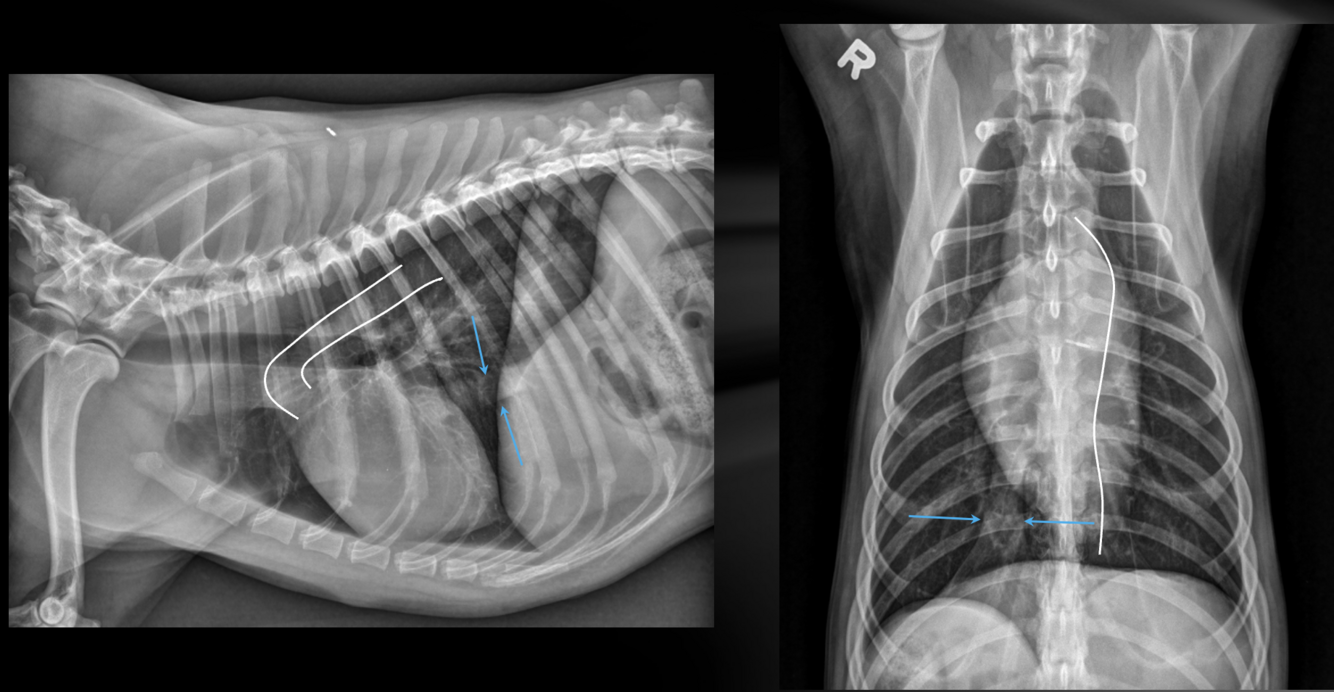

Which structures are outlined in these images?

A

white: aorta

blue arrows: caudal vena cava

What are the characteristics of the caudal vena cava?

-maximum normal diameter is approximately the same as the aorta

-will vary in diameter with cardiac cycle and phase of respiration

-if consistently small, think hypovolemia or shock

-if consistently large, think congestive heart failure